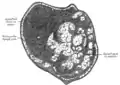

Additional images